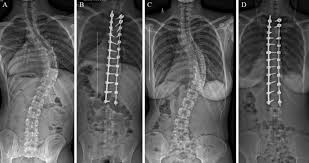

08042756842 - Physiotherapist for knee pain in Aundh | Physiotherapist Near Me |Physiotherapist for back pain in Aundh | Best physiotherapist for neck pain in Aundh |Physiotherapy Doctor in Aundh |Physiotherapy Clinic in Aundh | Physiotherapist in Aundh | Best Physiotherapist in Aundh | Physiotherapy Doctor in Aundh | Physiotherapy Treatment in Aundh | Chiropractor in Aundh | Physiotherapy for back pain in Aundh , Knee pain and injuries, neck pain, cervical and lumbar spondylitis or disc buldge,sciatica & shoulder injury and pain, muscle strain or sprain, arthritis | Geriatric | pregnancy Dr Sayli Kawatkar Is A Highly Rated and experienced Physiotherapist At Physio Studio Aundh Pune, with expertise in musculoskeletal injuries (spine,knee,shoulder and ankle rehabilitation )sports rehabilitation (ligament and muscle injuries with sports specific rehabilitation),post-operative care, women's health and geriatric care.